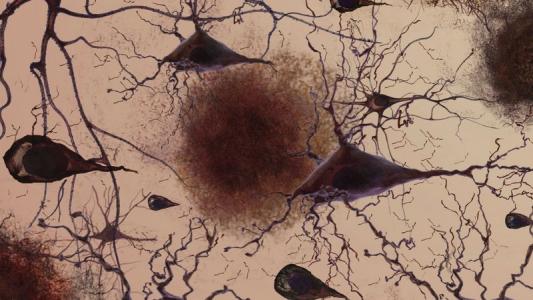

New evidence suggests viruses may trigger Alzheimer’s

For the first time in a long time, there's a new direction for potential Alzheimer's treatments.